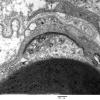

PERIPHERAL NEUROPATHY

7B CIDP (4)